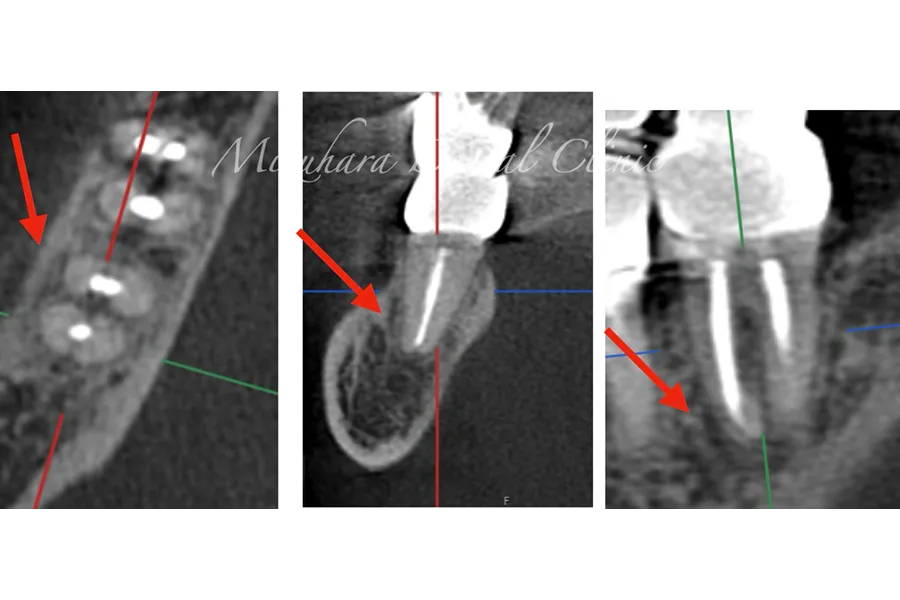

予知性の高い治療を提供できるだけ患者様の大切な歯を残し、10年、20年先まで健康な状態を保てるよう、長期的な視点で治療を計画します。そのために最も重要なのが、「診査」と「診断」です。的確な診断は精密な診査から生まれ、治療結果を大きく左右します。問診や簡易検査だけでは見逃されがちな病変も、CTやマイクロスコープなどの最新の医療機器を活用し、時間をかけて丁寧に「診査・診断」を行います。

世界基準の成功率を目指した精密根管治療

根管治療

当院では豊マイクロスコープ、ラバーダムを使用し、世界基準の成功率を目指した精密根管治療による「歯を残す」ための治療をご提供します。